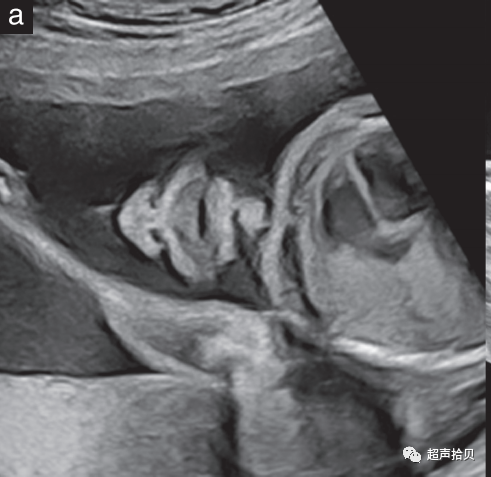

1. 手臂和手(图6a)以及腿和脚(图 6b ) 的存在与否 应使用系统方法进行观察记录;

2. 应检查所有四肢,注意所有长骨的存在及其对称性、长度、形状、对齐、位置和运动。

3. 作为孕中期常规超声检查的一部分,不需要计数手指或脚趾。

4. 通常,测量一根股骨就足够了,但如果有问题,则应测量所有长骨,并将测量值与标准化图表进行比较。

5. 标准检查中疑似偏离正常值应提示进行更详细的检查,以及可能的骨骼发育不良以及遗传和非遗传综合征的专家评估和咨询。

图6胎儿上(a)和(b)下肢的超声检查。上肢和下肢是否存在应常规观察记录,除非由于技术因素而不明显。